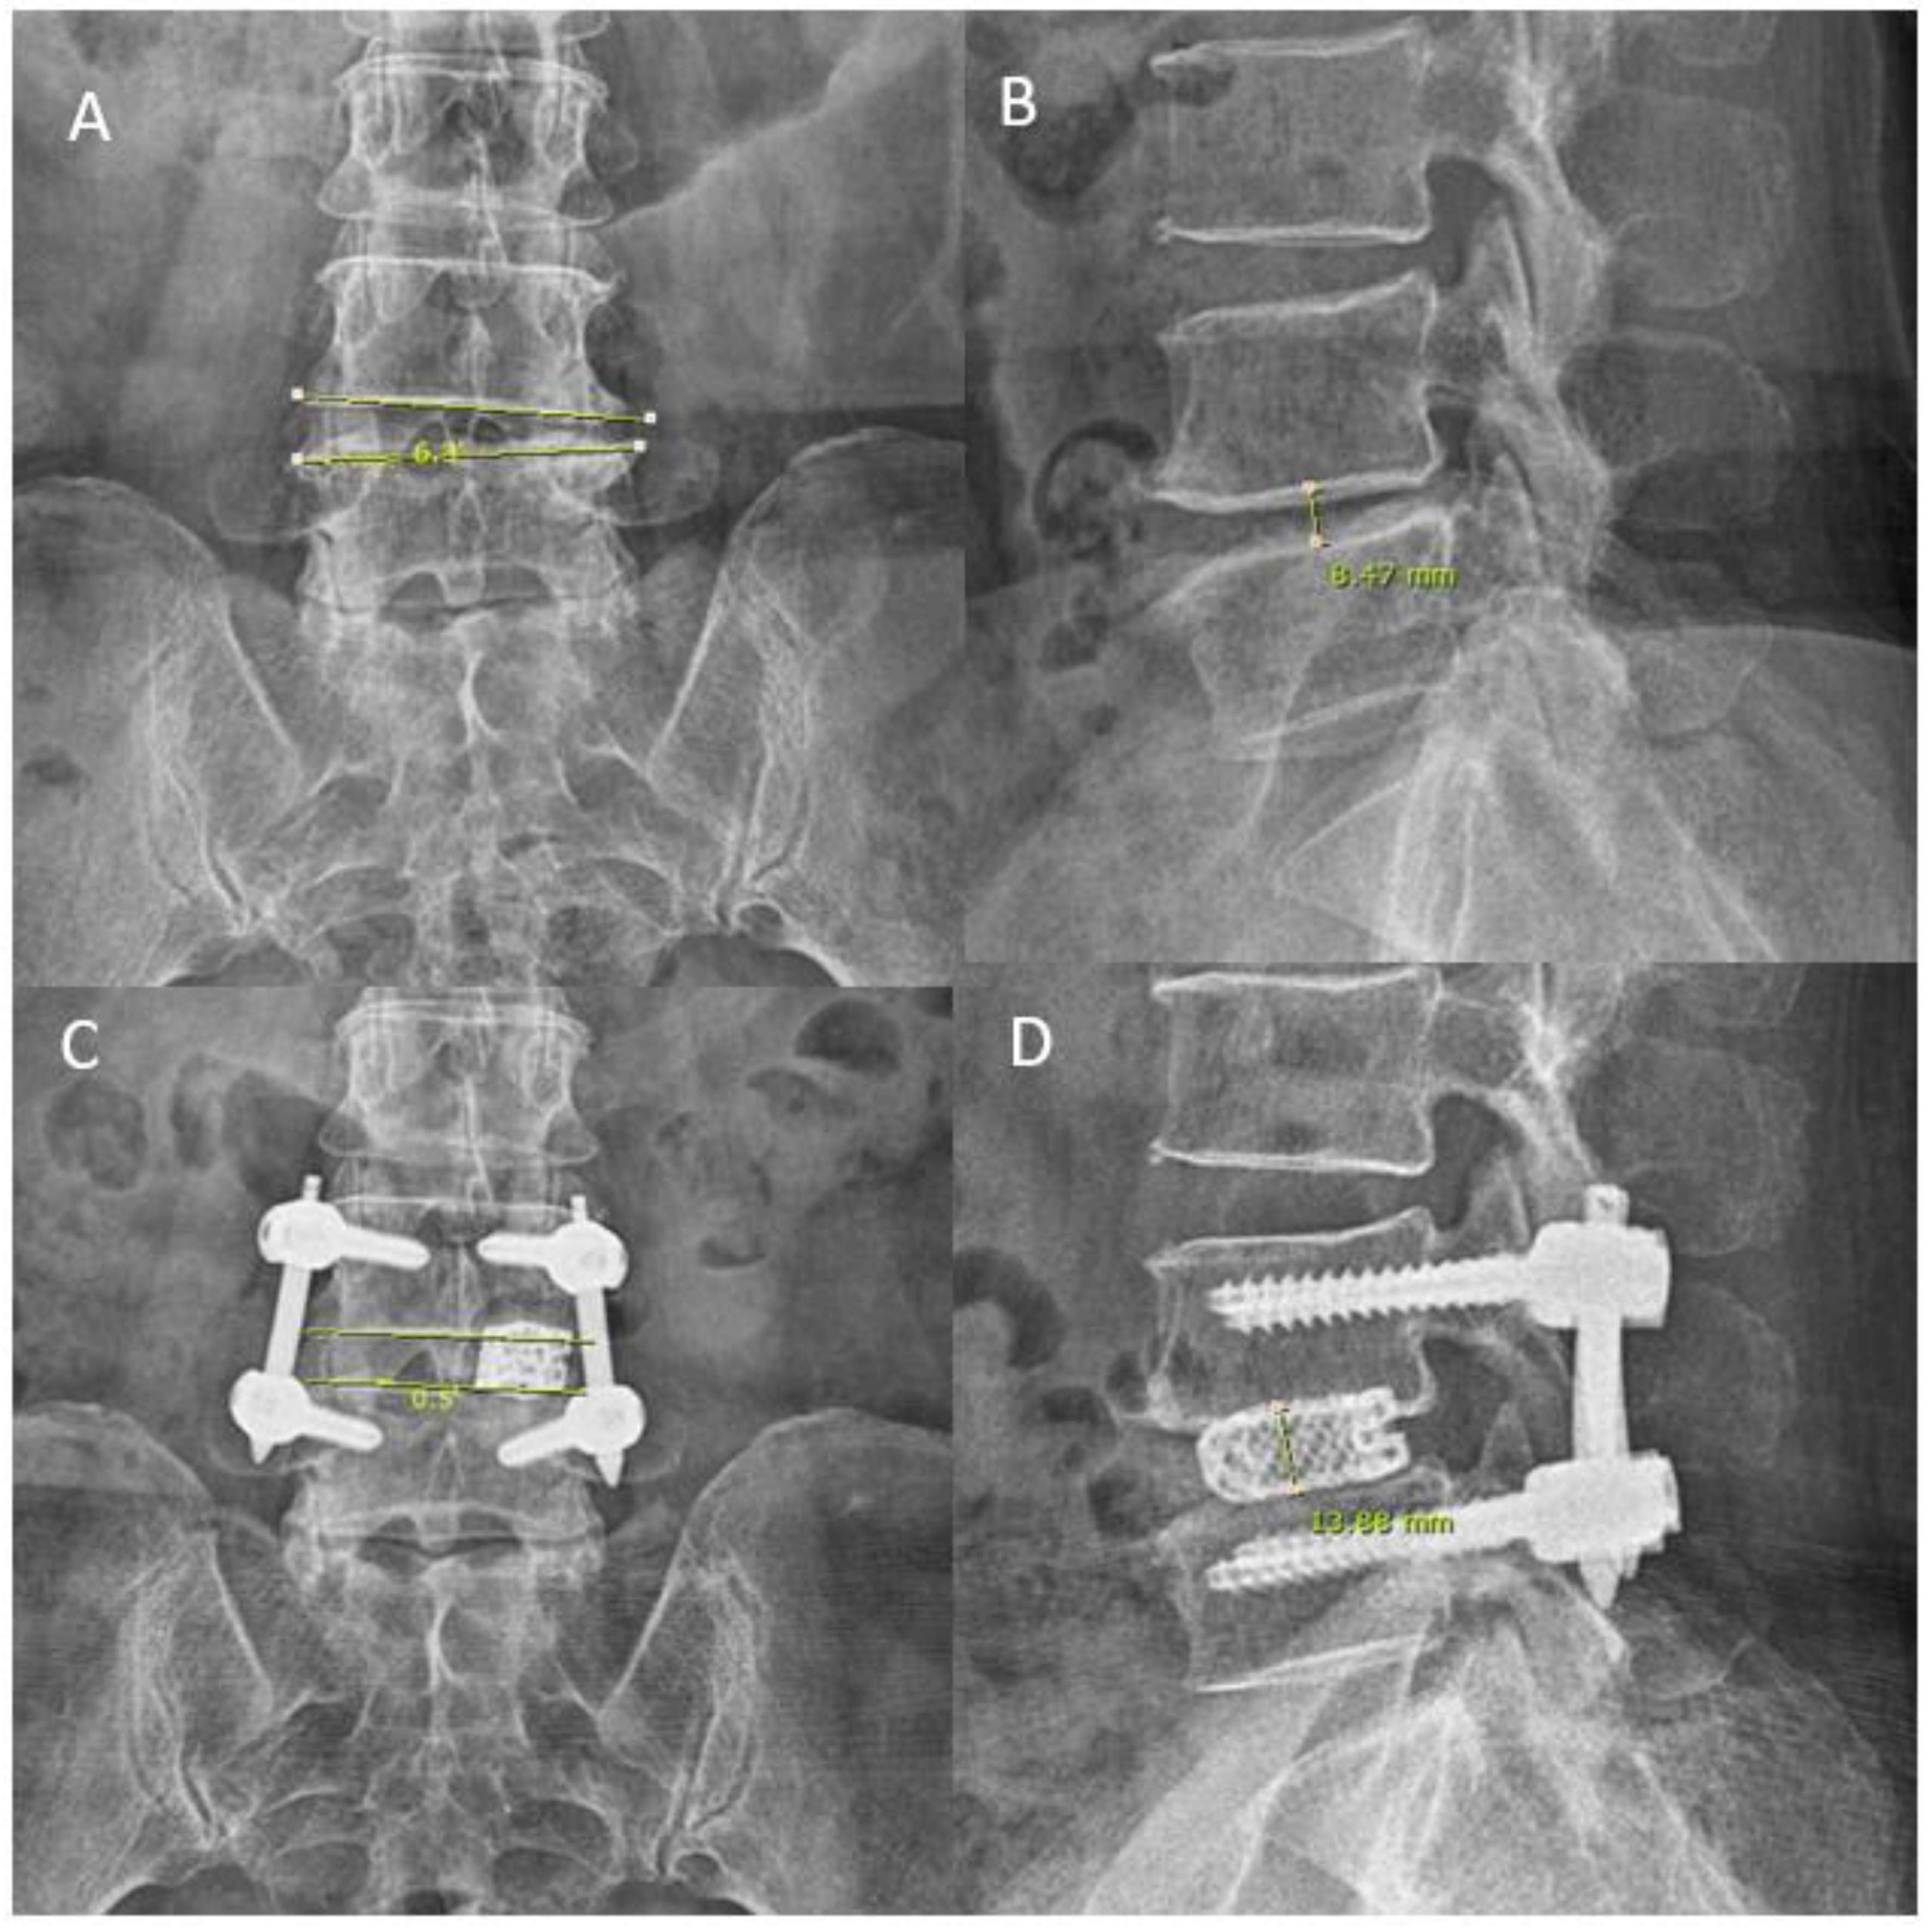

3.2. Intraoperative Timing and Radiological Parameters

| Disc Height Post-operatively (mean ± SD mm) | 12.25 ± 2.74 | 13.12 ± 1.88 | 0.097 |

| Coronal Wedging Pre-operatively (mean ± SD°) | 5.54 ± 3.75 | 6.09 ± 5.67 | 0.591 |

| Coronal Wedging Post-operatively (mean ± SD°) | 3.78 ± 2.73 | 2.85 ± 1.72 | 0.071 |

| Change In Disc Height(Postop-Preop) (mean ± SD mm) | 5.00 ± 2.87 | 5.49 ± 2.33 | 0.394 |

| Change In Cornoal Wedging Angle(Postop-Preop) (mean ± SD°) | 1.76 ± 1.63 | 3.24 ± 2.92 | 0.072 |